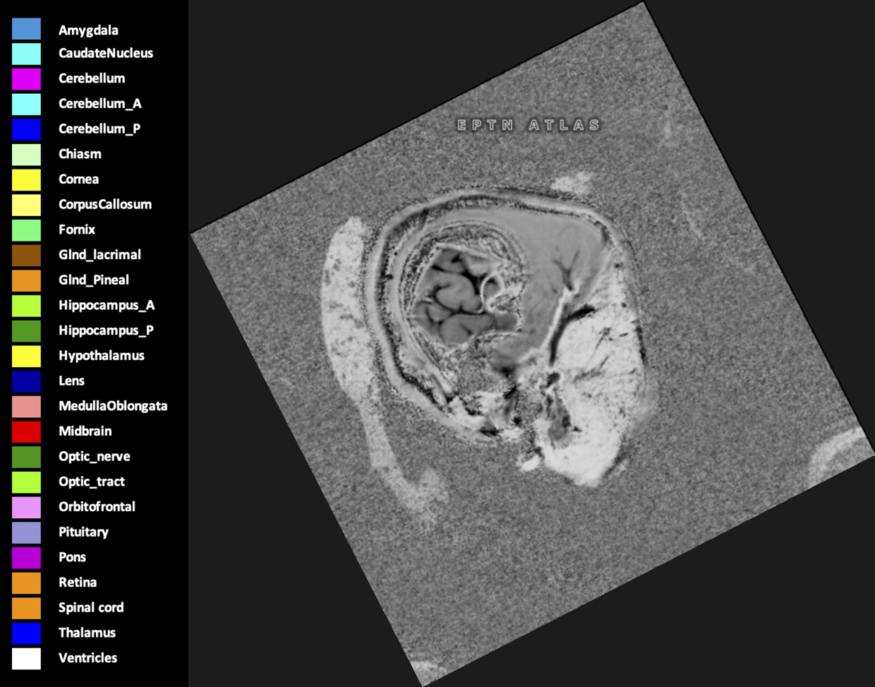

Included are all OARs known to be relevant for radiation-induced toxicity in neuro-oncology: brain, brainstem (midbrain, pons, medulla oblongata), chiasm, cerebellum (anterior & posterior), cochlea, cornea, hippocampus (anterior & posterior), hypothalamus, lens, lacrimal gland, optic nerve, pituitary, skin, and vestibular & semicircular canals. To further facilitate research on cognition, vision and radiological changes after irradiation of the brain, potential clinically-relevant OARs are included: amygdala, caudate nucleus, cerebellum (anterior & posterior), corpus callosum, fornix, macula, optic tract, orbitofrontal cortex, periventricular space (PVS), pineal gland, and thalamus.

Three-dimensional delineation of the 25 consensus OARs for neuro-oncology are shown on CT (WW/WL 120/40, 3000/600), 3T MR images, (T1Gd, T2FLAIR 1mm) and 7T MR (MP2RAGE 0.7 mm). All are presented in transversal, sagittal and coronal view.